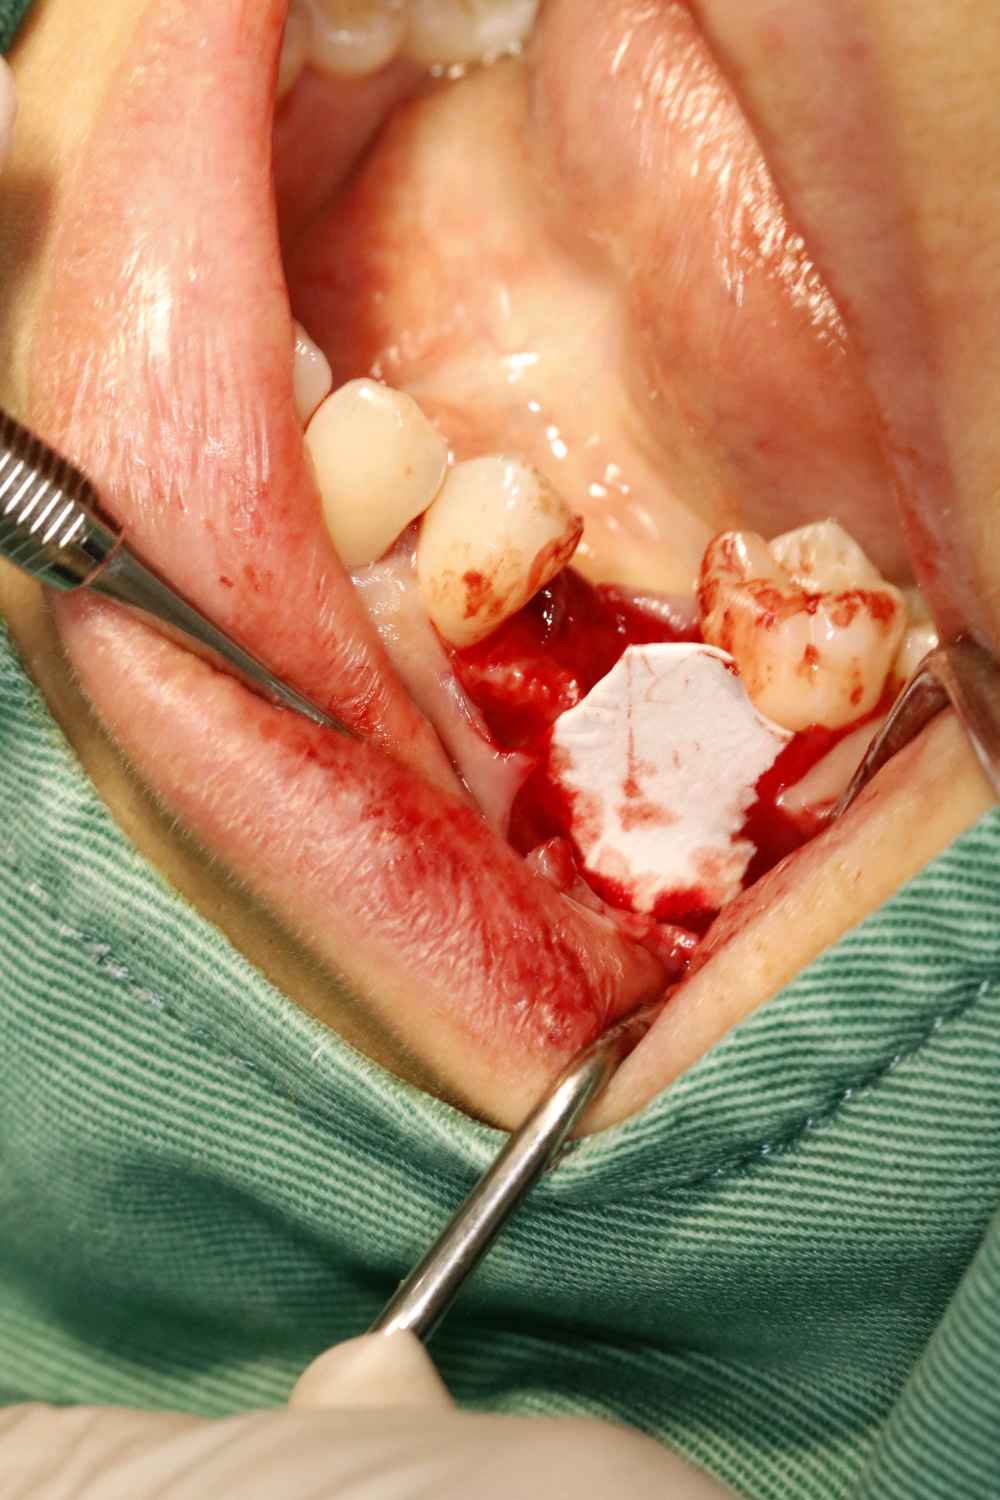

畸形中央尖多发生于下颌第二前磨牙,是一种牙体形态的发育异常,畸形中央尖本身不是什么大问题,只是折断或者磨穿了才会有不好的后果。这位患者就是因为没有长期的磨耗使的根尖周发生炎症时,导致根尖发育停止,根管口呈喇叭口状。对于这种牙根过短,根尖炎症范围过大的患牙,则考虑给予拔除。拔出后植入骨粉骨膜,后期种植修复。

术后